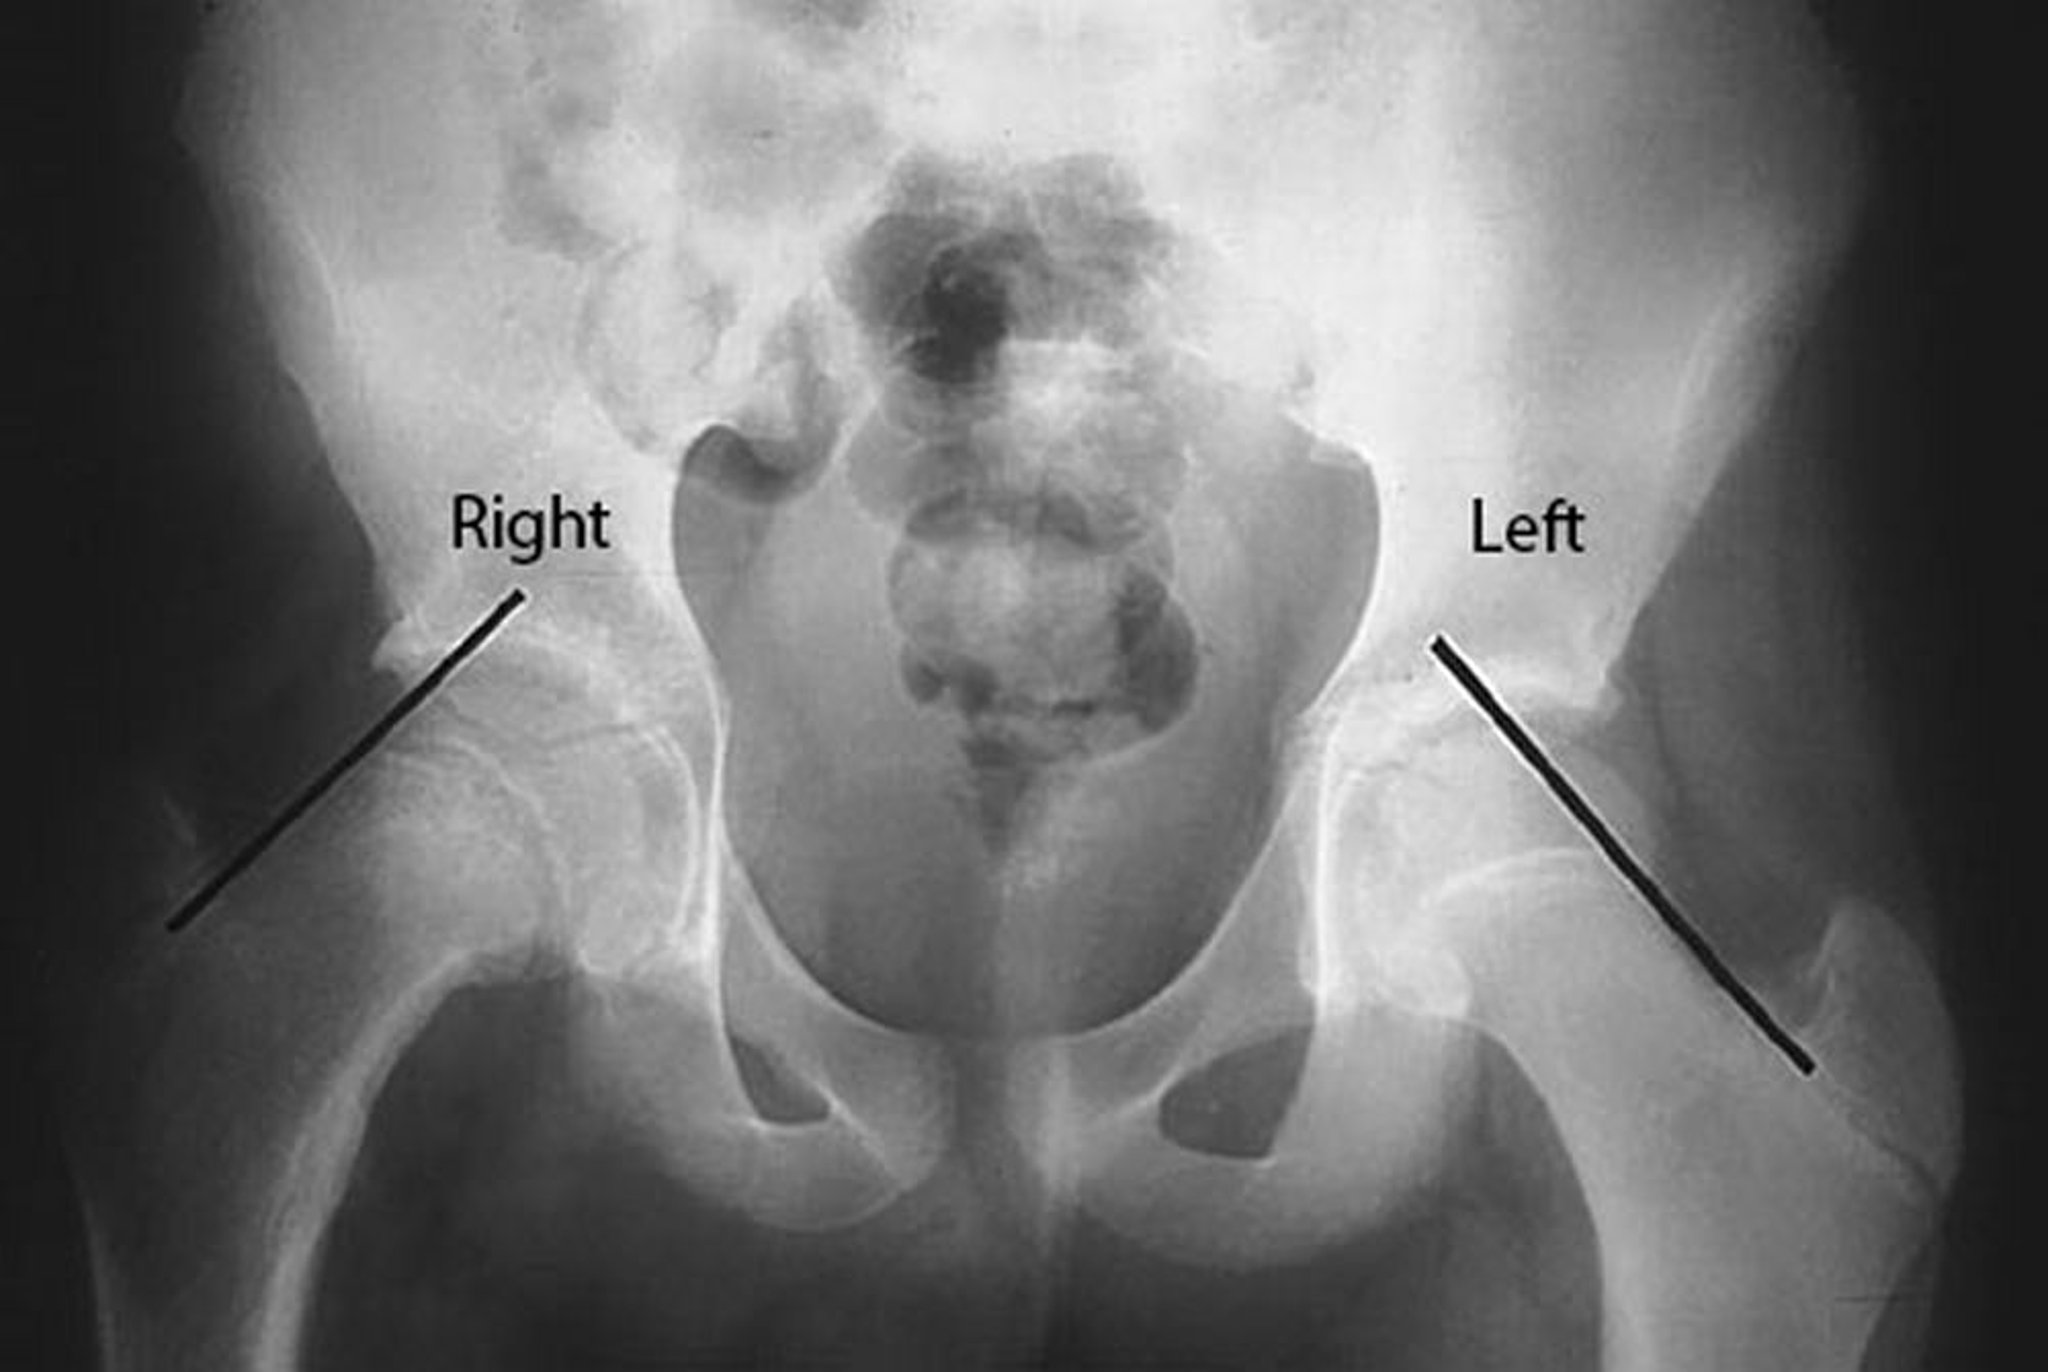

Chứng trượt đầu trên xương đùi (SCFE)

Các đường Klein được vẽ trên đường viền cao của cổ xương đùi ở bệnh nhân này bị trượt đầu trên xương đùi (SCFE) bị trượt ở hông phải. Lưu ý rằng đầu xương đùi nằm dưới đường Kline ở phía bên phải bị ảnh hưởng, trong khi một phần đáng kể của đầu xương đùi nằm phía trên đường Kline ở phía bên trái không bị ảnh hưởng.